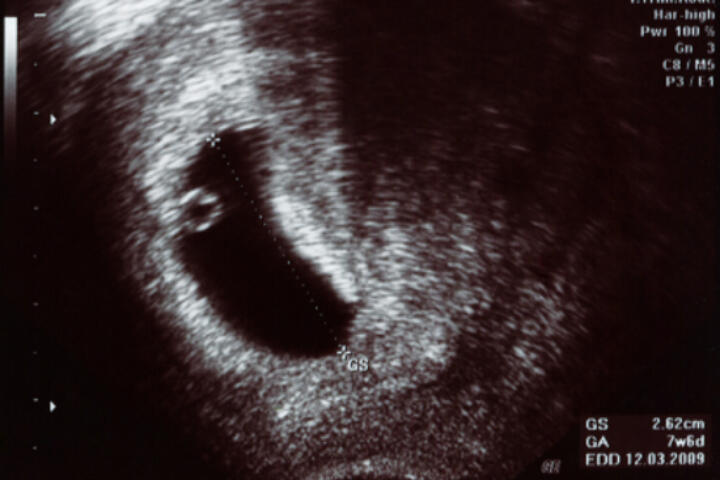

L’ecografia è una importantissima conquista nel campo della ginecologia perché permette di osservare il feto in modo non invasivo per tutta la gravidanza. Oggi esistono anche ecografie 3D (in tre dimensioni) e 4D (in tre dimensioni ma come filmato).

Le ecografie in gravidanza vengono fatte per monitorare lo stato di salute del bambino.  Non emettono radiazioni ma mandano onde ad altra frequenza attraverso la sonda ecografica. Le onde rimbalzano contro i tessuti solidi e vengono convertite in immagini, quelle che poi vediamo nel monitor dell'ecografista.

L'ecografia è un importante strumento diagnostico che permette di fornire immagini bidimensionali dell'anatomia fetale. Si chiama ecografia perché utilizza le onde sonore ad alta frequenza per produrre immagini degli organi interni e del bambino che portiamo in grembo.